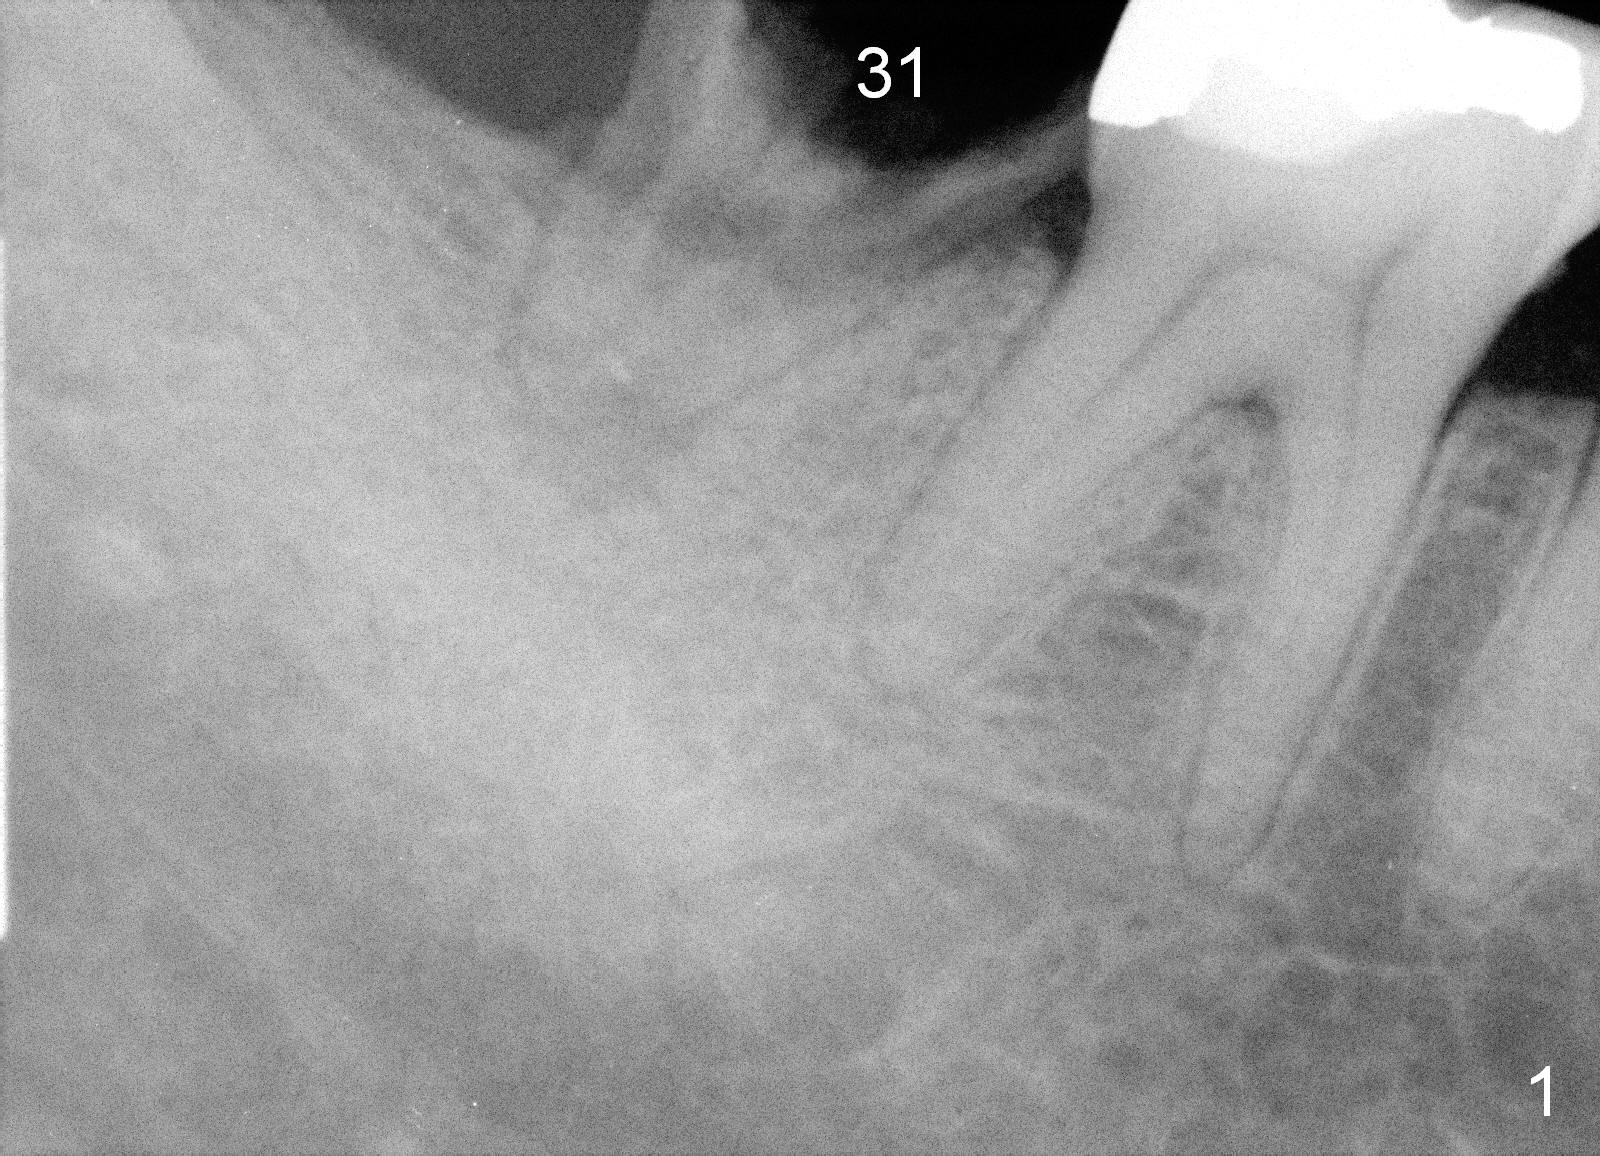

A 35-year-old man wants to restore the tooth #31. The root is conical in shape (Fig.1). It is natural to start osteotomy at the apex of the socket and along the long axis of the socket (Fig.2 red arrow), but the end result is that the immediate implant (Fig.3 black area) is not aligned well with the mesial and distal crests (pink areas; yellow dashed line: upper border of the Inferior Alveolar Canal). If this bone-level implant is level with the mesial crest, the distal threads will not be covered by the native bone. The distal threads may be exposed.